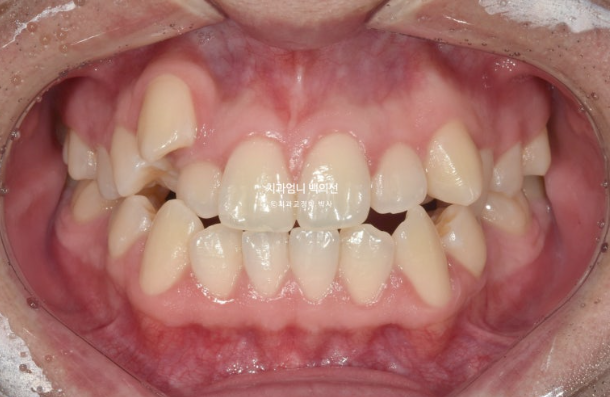

2022년 가을, 덧니 교정을 위해 오신 환자분입니다.

송곳니 덧니가 심합니다. high canine 하이캐나인 이라고 합니다.

덧니가 심해서 작은어금니 4개 발치가 불가피한 상황입니다.

인비절라인으로 치료 시작했으며 장치제작기간을 한달 반을 기다려 10월부터 인비절라인 1번 장치를 끼기 시작했습니다.

이제 전 후 비교 보겠습니다.

22.09~25.04